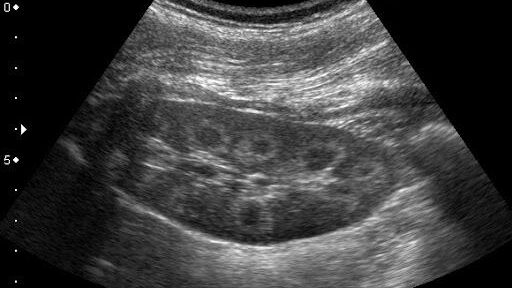

Ультразвуковое исследование почек даёт возможность быстро и безболезненно определить ряд заболеваний, которые на ранних стадиях развиваются скрытно. Есть симптомы, которые могут стать причиной для назначения данного обследования:

Заболевания, которые выявляет ультразвуковая диагностика почек

- нефроптоз

- гидронефроз

- амилоидоз

- опухоли, кисты

- воспалительные процессы (гломерулонефрит, пиелонефрит)